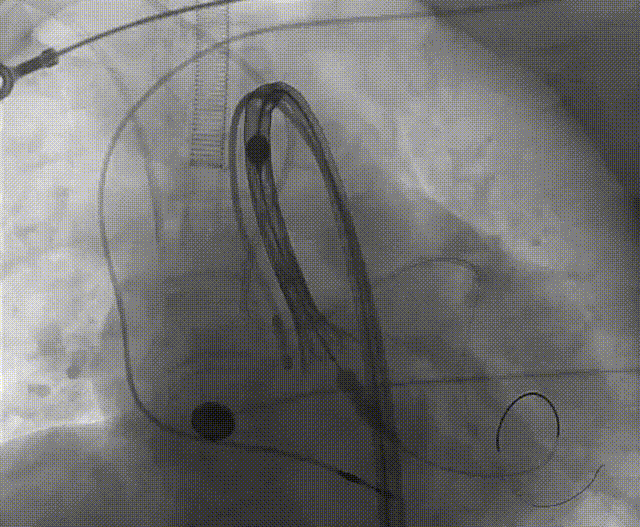

手术流程概括

22球囊扩张,无明显腰增,无造影剂泄露。

瓣膜初始零位释放,释放后位置尚可,决定完全释放。

瓣膜释放后有瓣周漏显示决定进行球囊后扩。

后扩后形态良好,瓣膜展开充分,轻微瓣周漏。